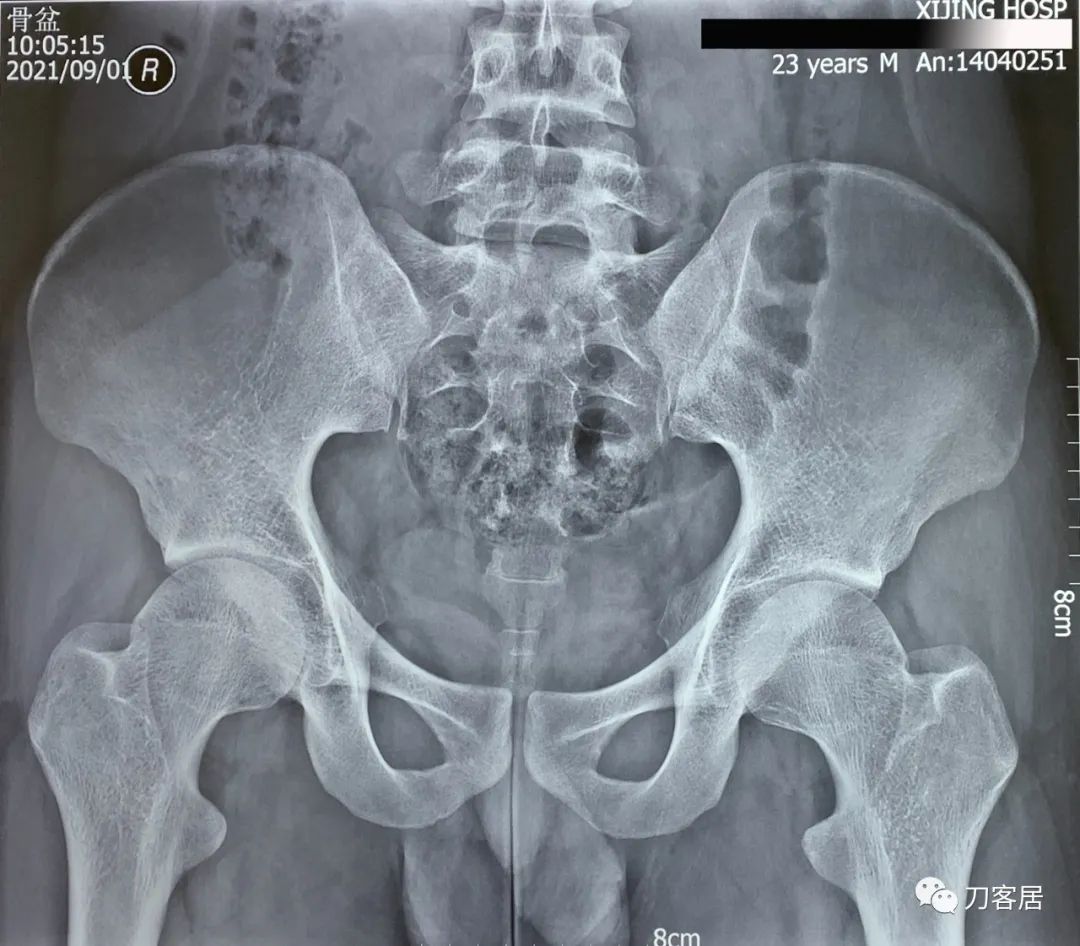

给患者查骨密度,提示骨量减少,T值最低-1.7。骨盆X线正位片提示腰5骶1隐裂。

图7. 20210901西京医院骨盆平片。

图8. 20210901西京医院骨盆平片报告。

诊断:单侧腰5峡部裂,骨质疏松症。